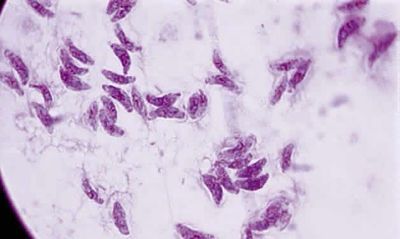

T. gondii este ubicuitara la pasari si mamifere. Acest parazit conditionat intracelular invadeaza si se inmulteste asexuat ca tahizoiti in citoplasma oricarei celule nucleate. Cand imunitatea gazdei se manifesta, inmultirea tahizoitilor inceteaza si se formeaza chisturi tisulare, care persista ani, mai ales in creier si muschi. Reproducerea sexuata a lui T.gondii are loc numai in tractul intestinal al pisici. Oochistii rezultati eliminate prin fecale raman infectiosi in solul umed timp de mai multe luni.